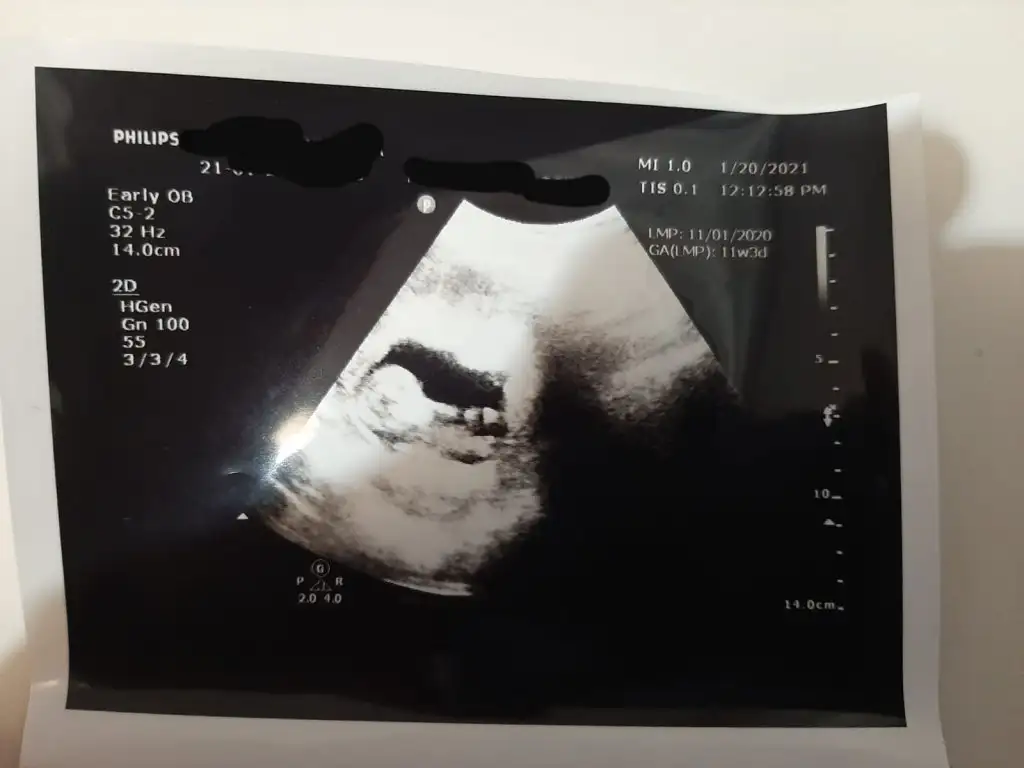

Merhaba Ikra meyra Ikra meyra bana da bakmanız mümkün mü acaba hem 11+3 hem 12+1 haftalık resimleri attım

Eklentiler

• IMG-20210126-WA0014.webp

IMG-20210126-WA0014.webp

26,9 KB · Görüntüleme: 66

• IMG-20210126-WA0013.webp

IMG-20210126-WA0013.webp

18,7 KB · Görüntüleme: 49

• IMG-20210126-WA0012.webp

IMG-20210126-WA0012.webp

26,6 KB · Görüntüleme: 44

• IMG-20210126-WA0011.webp

IMG-20210126-WA0011.webp

17,6 KB · Görüntüleme: 47